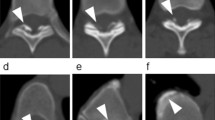

A 58-year-old-woman with thoracic HPLL was reported. Magnetic resonance image (MRI) and computed tomography (CT) showed the expanded spinal cord compression from Th4 to Th12 due to HPLL. Anterior decompression and fusion (Th10–12) was performed. Histological findings of the surgical specimens showed thickening of the posterior longitudinal ligament with proliferation of chondroid tissue. The clinical outcome and the radiological findings (CT and MRI) were evaluated 10 years after surgery.

The patient was asymptomatic postoperatively. However, the subsequent CT examination revealed ossification of the previously hypertrophied posterior longitudinal ligament.